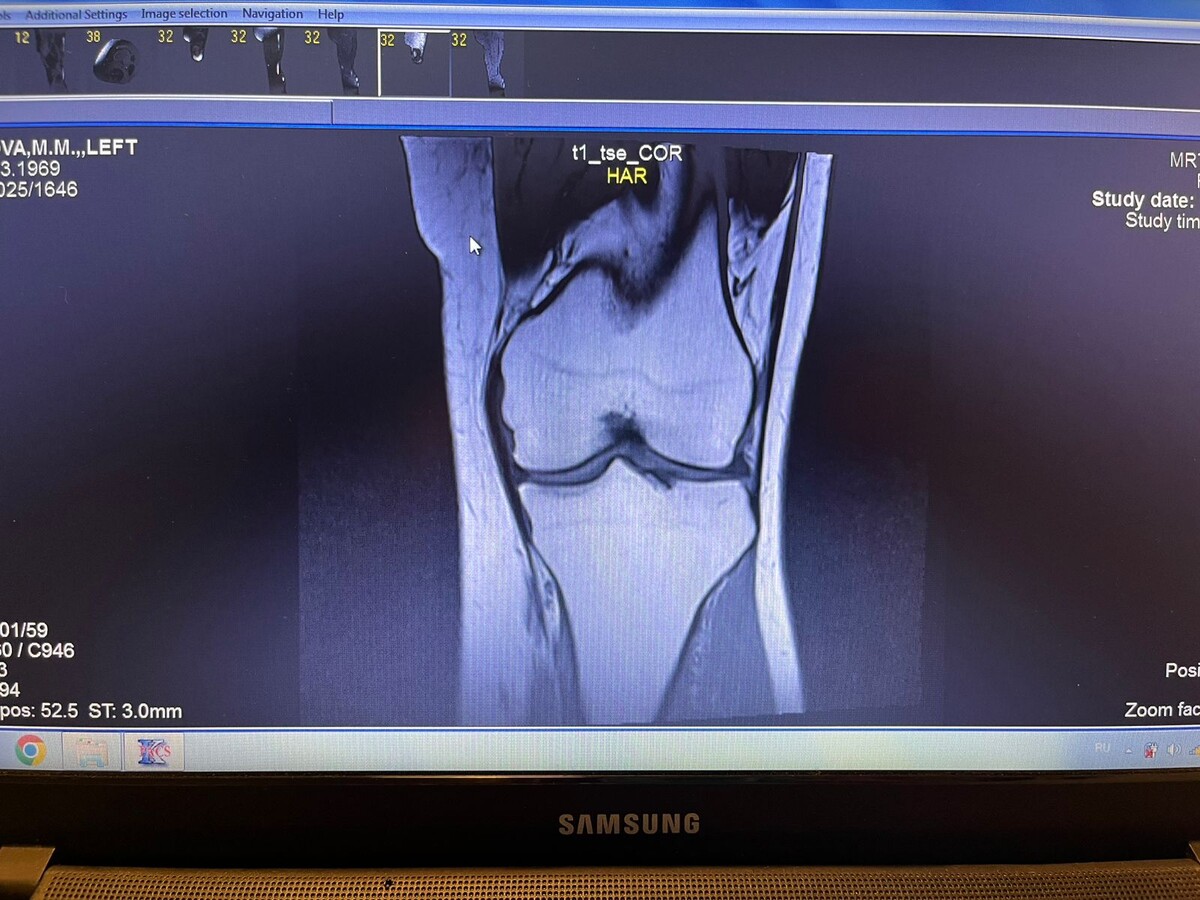

Мое любопытство и погружение в изучение проблем моего здоровья колен привело к следующему... На днях ко мне пришла соседка - молодая женщина 30+, мамочка годовалой малышки. Она постоянный мой Заказчик и большой любитель МОТИ. Кстати, о них и обо всем вкусном можете посмотреть на моем кулинарном канале Разговорились за жизнь и переключились на здоровье. Оказалось, что у моей юной собеседницы и коксартроз и проблемы с коленями, и во время беременности всё это очень усложнило состояние её здоровья. Она проходила много обследований и сама пыталась все рассмотреть на снимках МРТ потому что врачи ей говорили что все ок, и вы почаще отдыхайте и меньше ходите. Не высмотрела. Но у нее на компе стояла спец программа для просмотра диска МРТ. Она предложила мне тоже посмотреть мои "фото". Конечно мне любопытно. Я взяла её ноут с дисководом и воткнула свой диск..... Ооооо) любопытно дальше некуда - масса фотографий , и если прокручивать колесико мышки получается как видео с увеличением и приближени

Ооооо) любопытно дальше некуда - масса фотографий , и если прокручивать колесико мышки получается как видео с увеличением и приближением деталей.

Но ничего не понятно, несмотря на то что я читала в интернете и смотрела примеры. Дааа, утвердилась я - это только для врачей.

И он мне подробно рассказал и обьяснял несмотря на свою занятость. Я поняла что на МРТ послойные срезы ( как нарезной батон, примитивное сравнение , но как есть) проблемной зоны, и благодаря этому можно диагностировать состояние и поставить правильное заключение. То, что мне написали в заключении - там есть "страшные" слова, которые пугают обывателей "дегенеративностью", на самом деле это пишут почти в 70% заключений и это не представляет особой опасности для здоровья. надо просто им, здоровьем, заниматься.